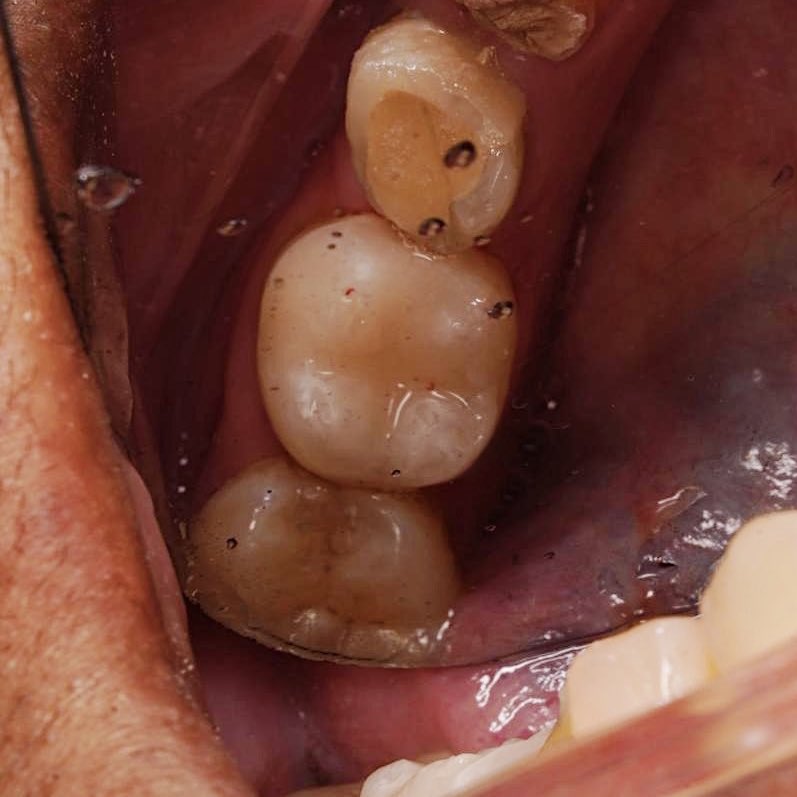

Successfully completed endodontic treatment on #36 with Radix Entomolaris, a challenging and rewarding case ✨

Grateful to have performed it under the supervision of @DrKhawlahSays and @HananShu

Thank you for your guidance and continuous support in advancing our clinical skills.